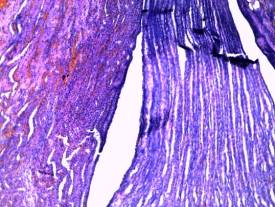

-

capillaries of nephrons and intersticial tissue in kidneys are

plethoric, cytoplasm of kidney proximal tubule epithelium is oxyphilic, cell’s

borders are distinguishable, nuclea are bright and clear (picture 3);

Picture 3

Histological

research results

(plethora of kidney

tissue)